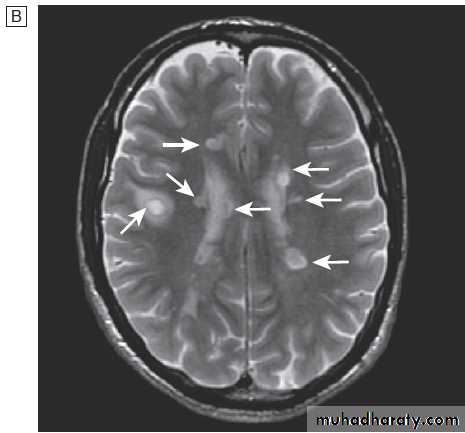

render posterior fossa CT images less useful, and CT is less sensitive to white matter changes than MRI.

MRI resolution is unaffected by bone and so is more

useful in the investigation of posterior fossa disease. Its sensitivity to cortical and white matter changes makes it effective in picking up inflammatory conditions such as multiple sclerosis, and in investigating epilepsy.